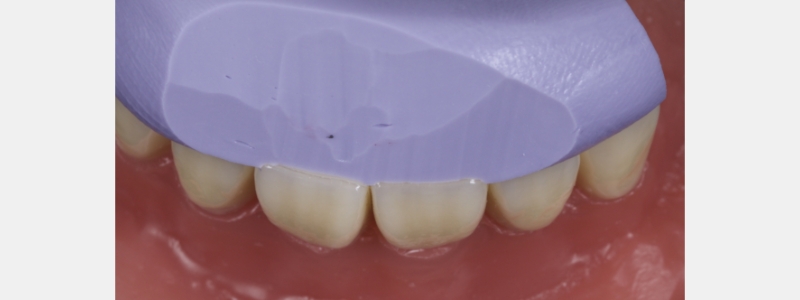

In this case, a young patient in his early 20s presents with discolored central incisors, multiple diastemas, and a canted incisal plane (Fig. 23).

A clear PVS stent was fabricated from a digital wax-up and filled with flowable composite (Fig. 24).

I prefer an opaque flowable composite for this application because a regular flowable composite tends to be quite translucent, making the underlying tooth structure visible, which distracts many patients. The flowable composite was polymerized, and the stent was removed.

The esthetics were assessed by the patient, and some adjustments were made to the distal line angles of the lateral incisors. When the patient was satisfied with the appearance, another sectional digital scan of the modified mock-up in the patient’s mouth was taken and stitched into the original scan to form the final mock-up (Figs. 25 and 26).